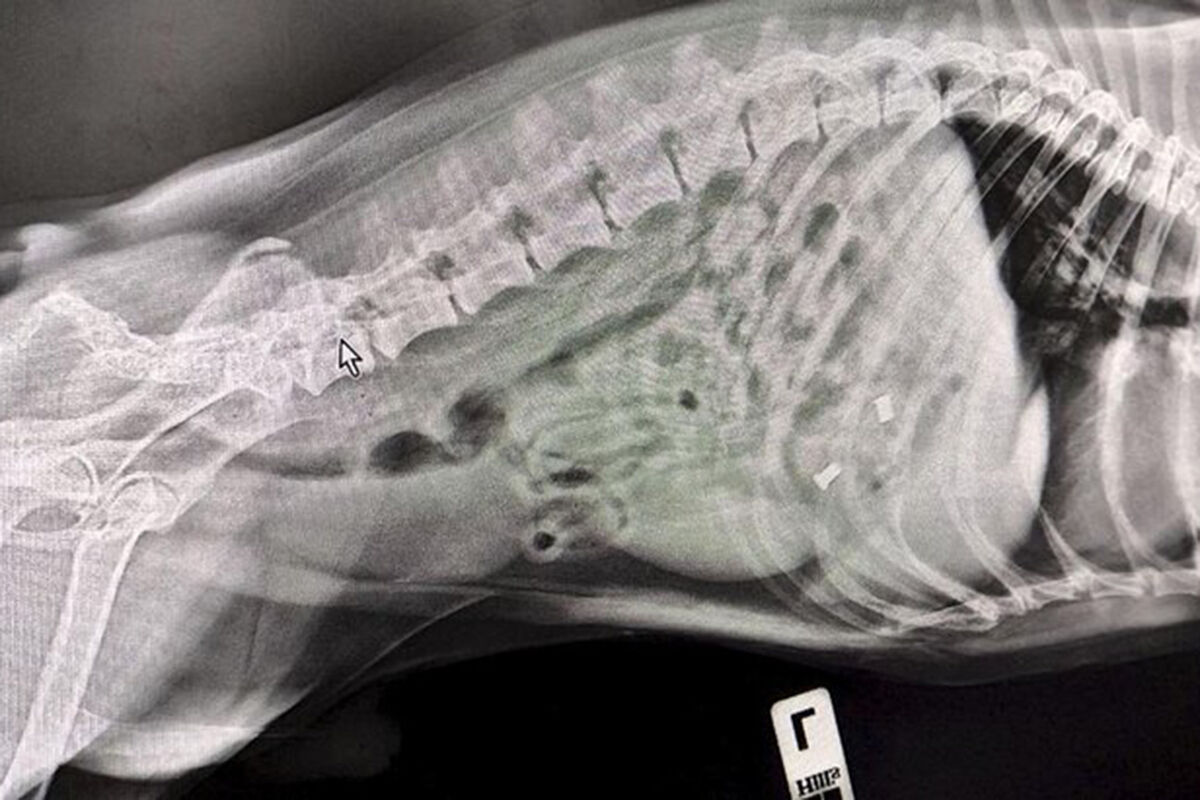

В пресс-службе ведомства уточнили, что владельцы привели к ветеринарам питомца по кличке Смайл с подозрением, что он съел игрушечного дракона. Терапевт Алексей Щукин и УЗ-диагност Елена Сухарева провели УЗИ и рентген. В ходе исследований стало понятно, что внутри собаки находится не один предмет.

«Поскольку Смайла доставили в ветклинику сразу же после происшествия, обошлось без операции. Специалисты вызвали медикаментозную рвоту и удалили предметы из желудка собаки», – отметили в пресс-службе.

Специалисты извлекли из Смайла кусок игрушки и итальянские серьги из муранского стекла. После этого его отпустили домой.